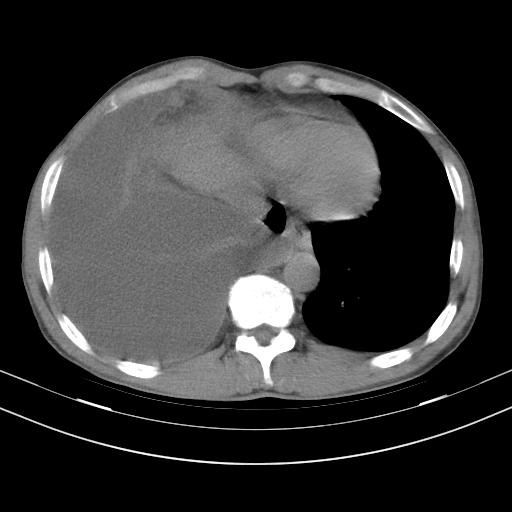

男性,44岁,结核病史多年。现胸闷气短,咳嗽,偶咳血。

右侧胸腔积液

右肺下叶不张

双肺多发结节影最分空洞形成考虑占位不除外结核

双肺陈旧性病变

1、右侧大量胸腔积液伴右肺压缩性膨胀不全,建议抽液治疗后复查 2、两肺继发性tb伴空洞形成。

1)两肺继发性肺结核伴空洞形成,左肺多发性结核球。2)右侧大量胸腔积液伴右肺部分膨胀不全。3)纵隔淋巴结肿大。